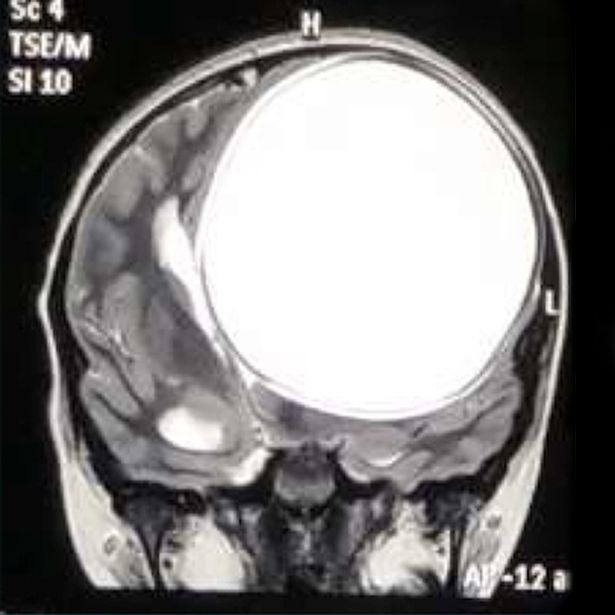

Một cô bé 12 tuổi đã khiến nhiều người sốc nặng khi mang thứ không ngờ này trong não. Sau khi được phẫu thuật, các bác sĩ đã lôi ra búi nang sán nặng 675 g chiếm tới hơn một nửa kích thước bộ não cô bé. Theo các bác sĩ cho biết thì đây là nang sán lớn nhất trong lịch sử y học.

Các bác sĩ Ấn Độ mới đây đã phẫu thuật bóc tách nang sán khổng lồ chiếm tới hơn một nửa kích thước bộ não trong đầu cô bé 12 tuổi và được cho là nang sán lớn nhất trong lịch sử y học.

Hai tháng trước, cô bé được đưa tới gặp bác sỹ Chirag Solanki, một chuyên gia thần kinh và là bác sỹ phẫu thuật cột sống, tại bệnh viện Sterling ở Gujarat. Sau quá trình kiểm tra kỹ lưỡng và chụp cộng hưởng từ, họ phát hiện một nang sán khổng lồ trong não cô bé.

Nang sán này nặng 675 g và có kích thước 12,2x11x9,8 cm. "Tôi cho rằng bọc nang này đã phát triển trong đầu cô bé cách đây 8-10 năm. Càng phình to ra, nó càng gây ảnh hưởng nhiều và khiến cơn đau đầu ngày càng dữ dội”, bác sĩ nói.

“Nang sán này to bằng một nửa kích thước bộ não, trông như một quả bóng căng phồng và rất nguy hiểm bởi nó có thể vỡ bất cứ lúc nào, khiến cô bé tử vong ngay lập tức”. Bác sĩ Solanki nói gia đình cô bé rất sốc khi biết con gái mình mang một ổ nang sán lớn đến như vậy.